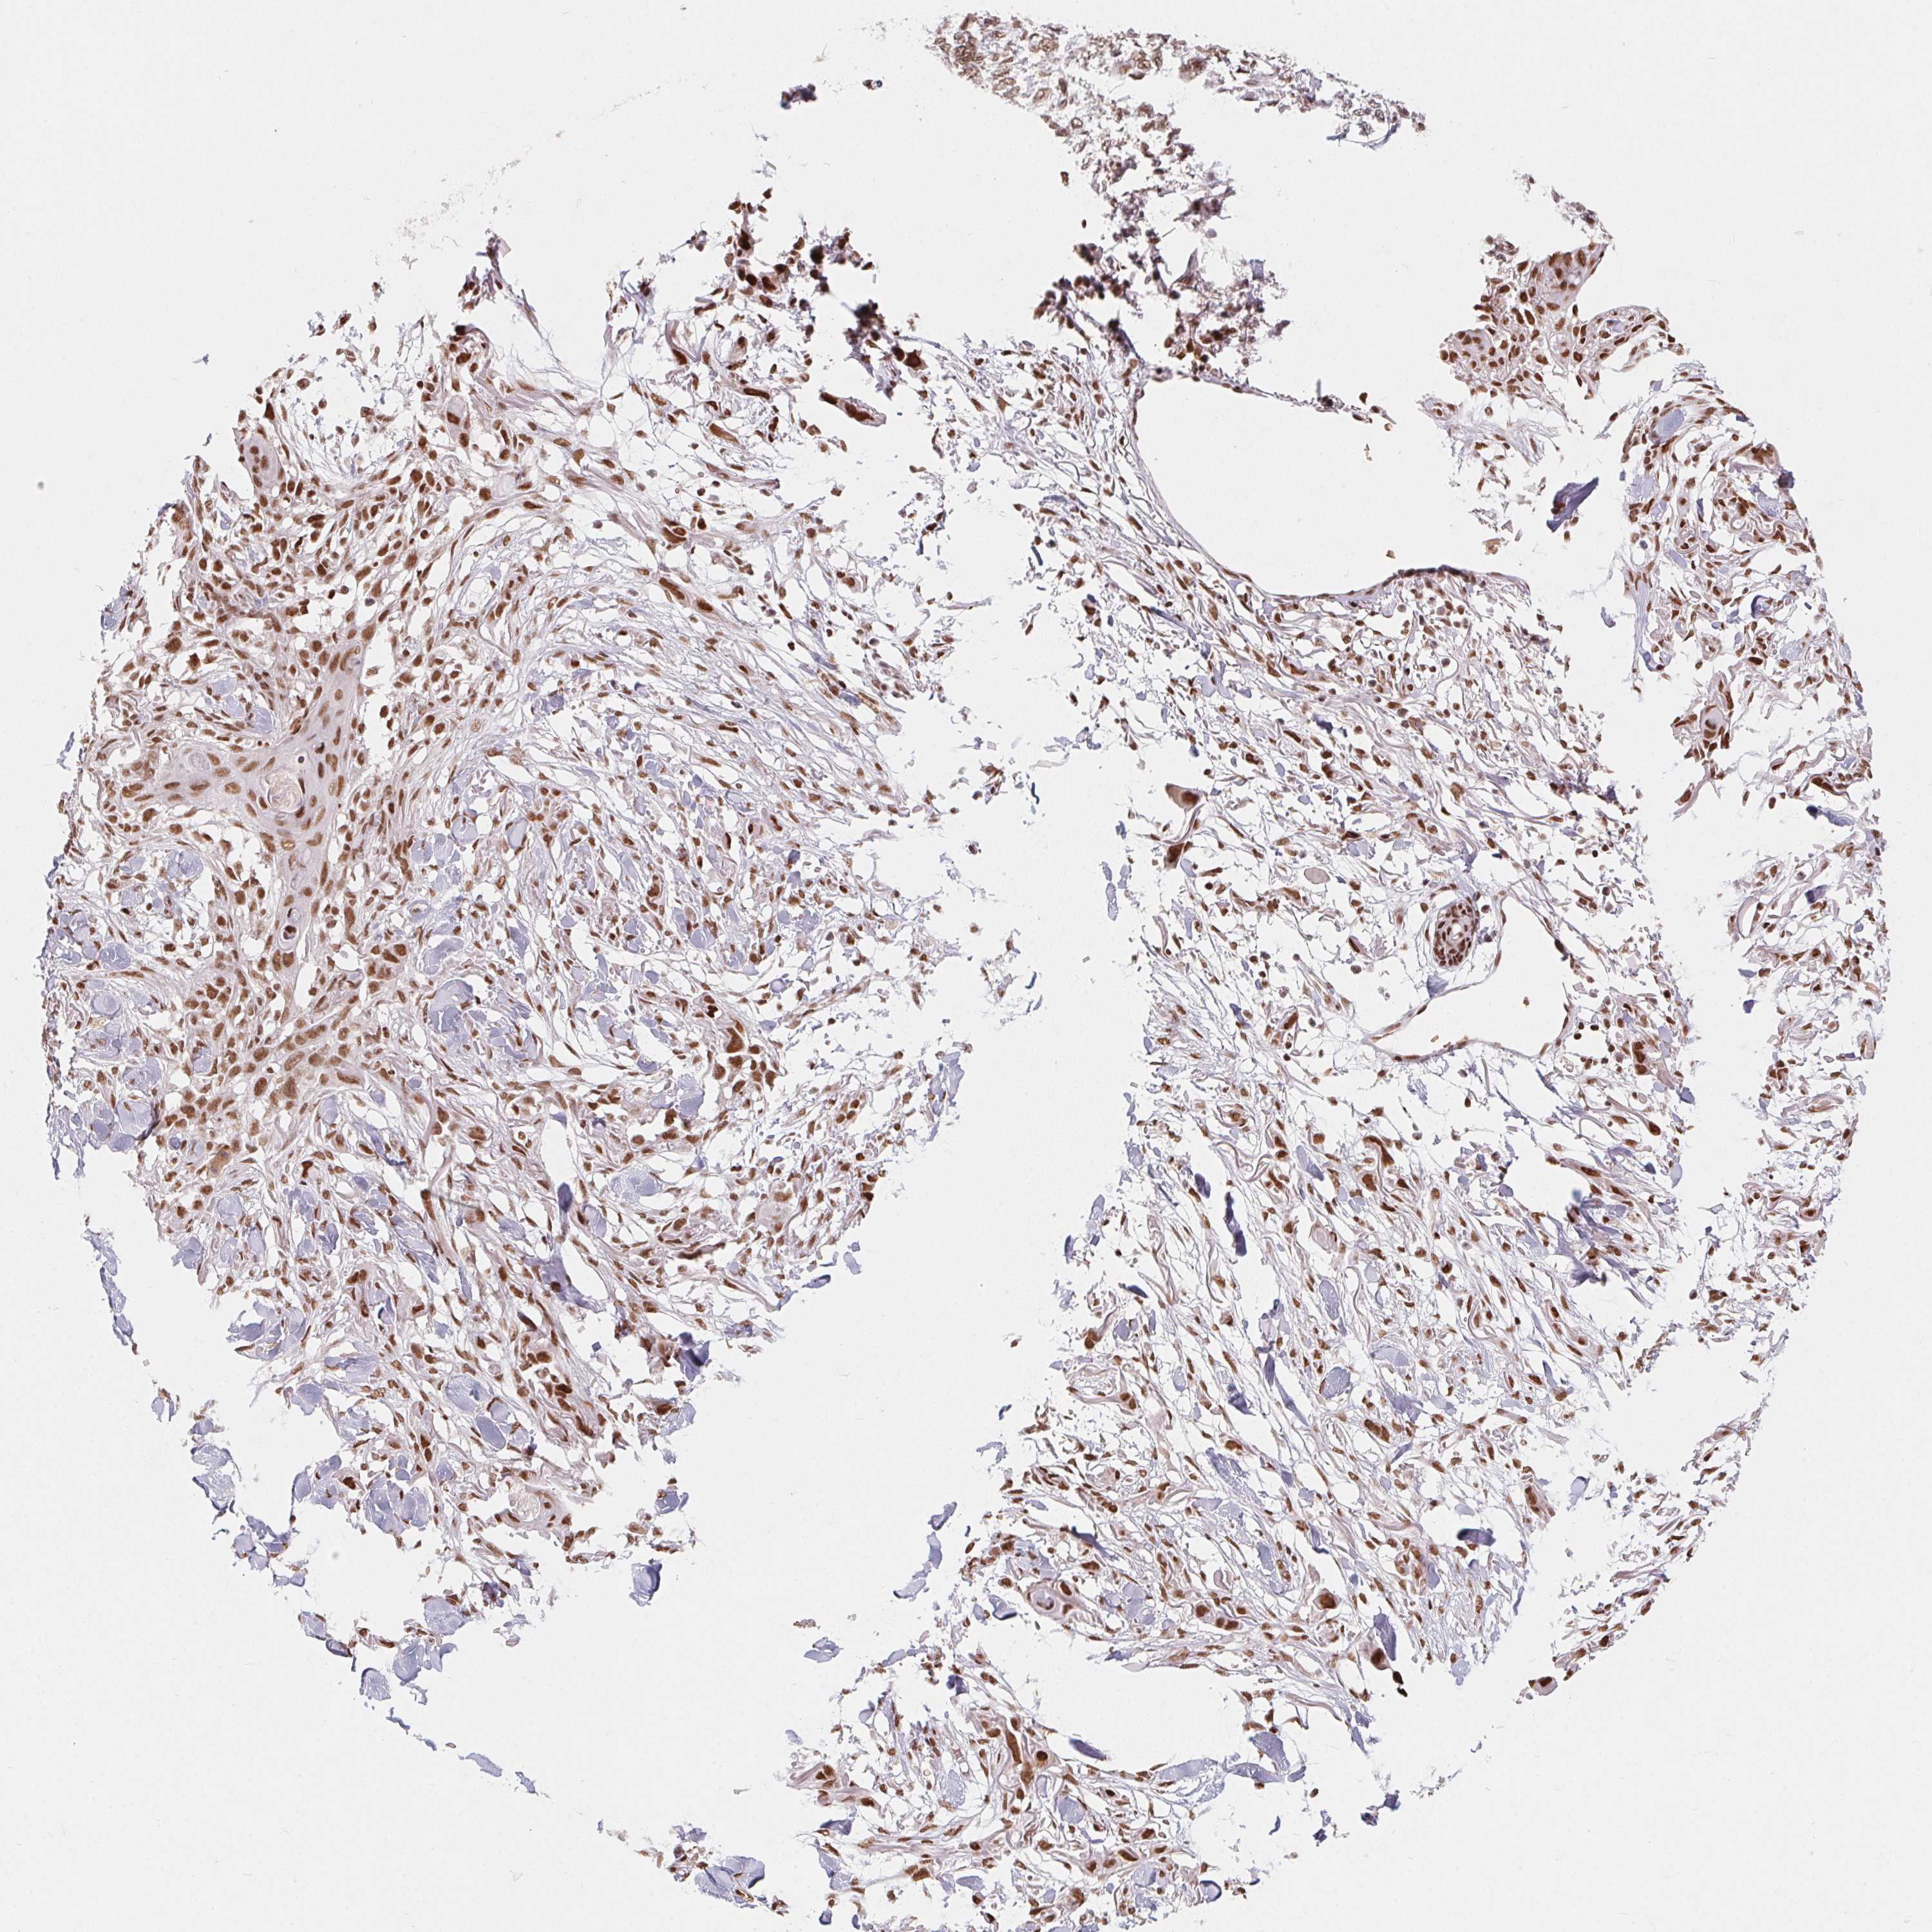

SKIN CANCER - Protein expressioni

A mouse-over function shows sample information and annotation data. Click on an image to view it in a full screen mode. Samples can be filtered based on level of antibody staining by selecting one or several of the following categories: high, medium, low and not detected. The assay and annotation is described here.

Each image is clickable and will lead to virtual microscopy that enables deeper exploration of all samples and also displays staining intensity scores, fraction scores and subcellular localization as well as patient and tissue information for each sample.

Antibody HPA064887

Staining

High

Medium

Low

Not detected

Intensity

Strong

Moderate

Weak

Negative

Quantity

>75%

75%-25%

<25%

None

Location

Nuclear

Cytoplasmic/membranous

Cytoplasmic/membranous,nuclear

Basal cell carcinoma